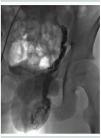

La tomografía contrastada de abdomen (figura 1) mostró pinzamiento de la vena renal izquierda entre la arteria aorta y la mesentérica superior, hallazgos sugestivos de este síndrome, por lo que se realizó cavografía y venografía renal izquierda, confirmando los hallazgos típicos del síndrome de Nutcracker, debido a la persistencia de hematuria grave que lo comprometía hemodinámicamente a pesar de las transfusiones sanguíneas, el paciente fue sometido a terapia endovascular consistente en colocación de stent en el sitio de plicatura, con mejoría de la hematuria macroscópica a las dos semanas postratamiento.

Figura 1. Tomografía contrastada de abdomen, fase arterial tardía. Se observa disminución marcada del calibre de la vena renal izquierda en su recorrido entre la arteria mesentérica superior y la aorta debido a la disminución en el ángulo aortomesentérico causando